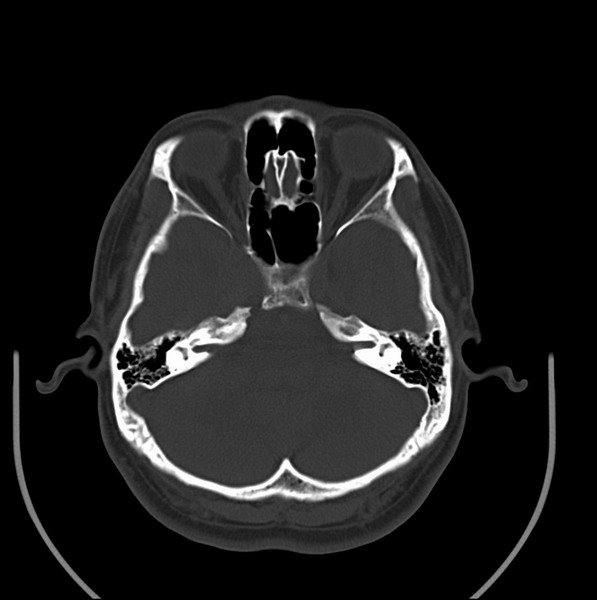

男、30、发现鼻咽部肿瘤侵犯海绵窦,未发现明显淋巴肿。请问国内那家医院治疗鼻咽部肿瘤最好?手术以何种方式为主?病灶可否全部切除?急切期待的大家的帮助。

扫描示鼻咽腔不对称,中度狭窄,右侧咽隐窝消失,局部软组织肿块,鼻咽右侧壁增厚形成肿块,突入鼻咽腔,肿块平扫呈等密度,肿块向深部侵润,右侧翼内外肌受侵,右侧咽旁间隙变窄;向后生长,头长肌界线欠清,向后上生长侵犯同侧颈动脉鞘区。双侧海绵窦增宽,内见软组织影与鼻咽部肿块相连。考虑鼻咽癌。鼻咽癌主要是放射治疗,且效果较好;到当地有治疗设备较大医院治疗即可。

这个病例有点特殊,和常见的鼻咽癌不太一样,以向颅内侵犯为主,骨质破坏区小。鼻咽癌首先要考虑,有没有其他可能?本人不会看mr片,期待有人能讲解,期待病理。

鼻咽部新生物(纤维血管瘤?鼻咽癌?)侵犯右侧中颅窝底及右侧海绵窦;建议必要时活检定性。

鼻咽部新生物侵犯右侧中颅窝底及右侧海绵窦,鼻咽癌可能性大。建议增强扫描。纤维血管瘤禁忌穿刺。

典型鼻咽癌侵犯右侧海绵窦(对放疗敏感)